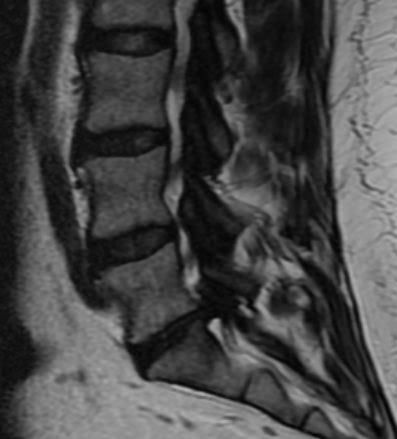

I just had an MRI done and they gave me a disk to take with me for a Doc that will be calling me.

Can anyone tell me how bad is it? Just a heads up on what can be expected.

I won't hold you to your diagnosis.

Yes, look at my lovely back fat.. Cracklins I say, Cracklins.